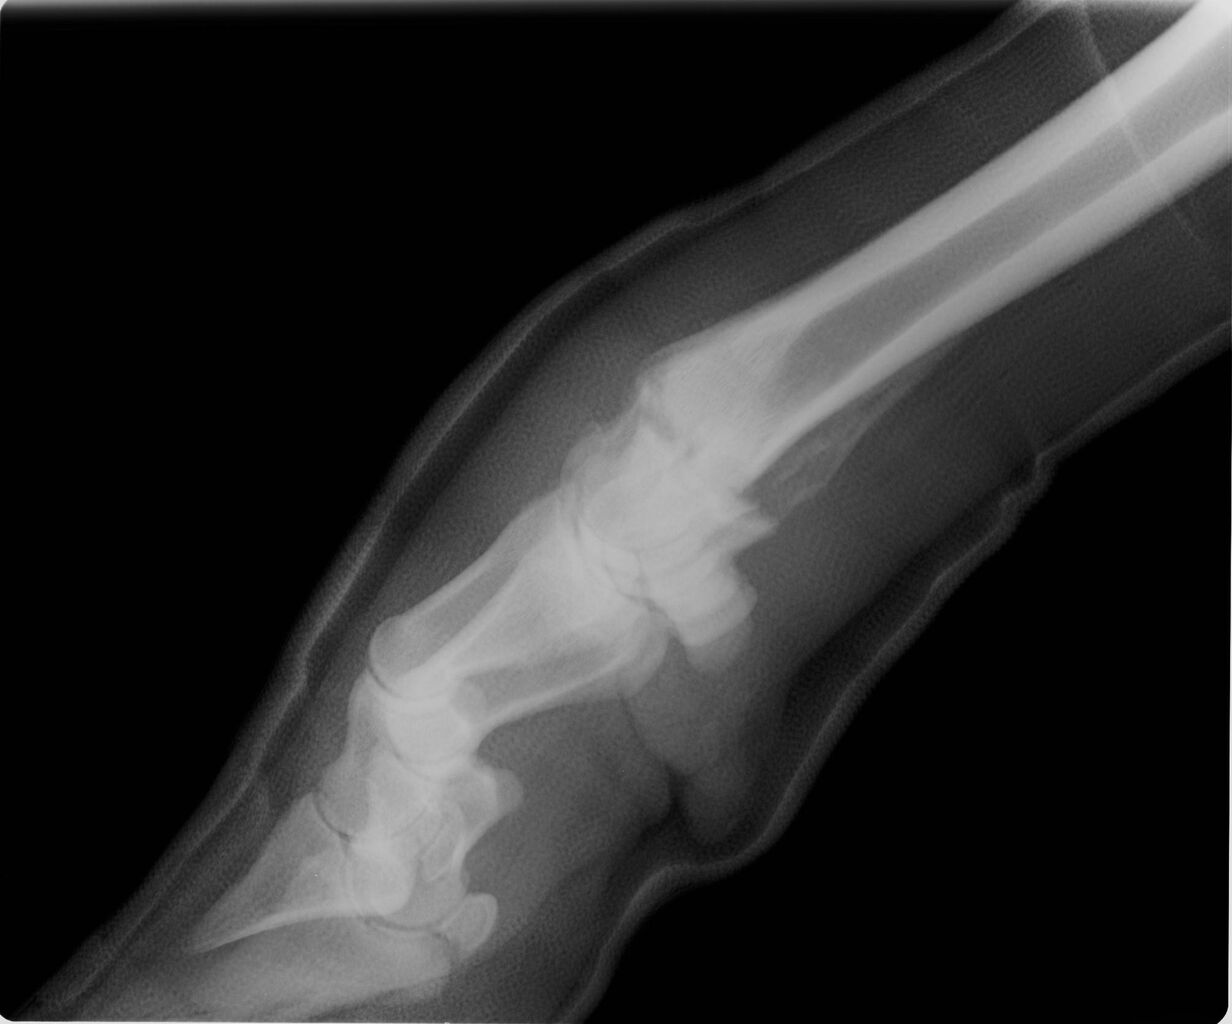

ドクター先生のリクエストにお答えして

外内方向のX線画像を

おまけとしてUP。

中足骨骨端と遠位成長板との間に

前後にもズレがあるかどうか

ドクターH先生の診断を

待ちたいと思う。

外内方向のX線画像もあったのでしたか?

牛は馬以上にきれいな外内方向のX線撮影が難しいですが、遠位成長板でのずれがなかったか気になります。

私たちが経験したホルスタイン470kgは、成長板でかなりずれていました。

牛はこのタイプの成長板損傷と骨端骨折がパターンとしてあるようですね。S-Hの分類にあてはまらないので、Mamesaku-Higのタイプ6として報告できるかも!?